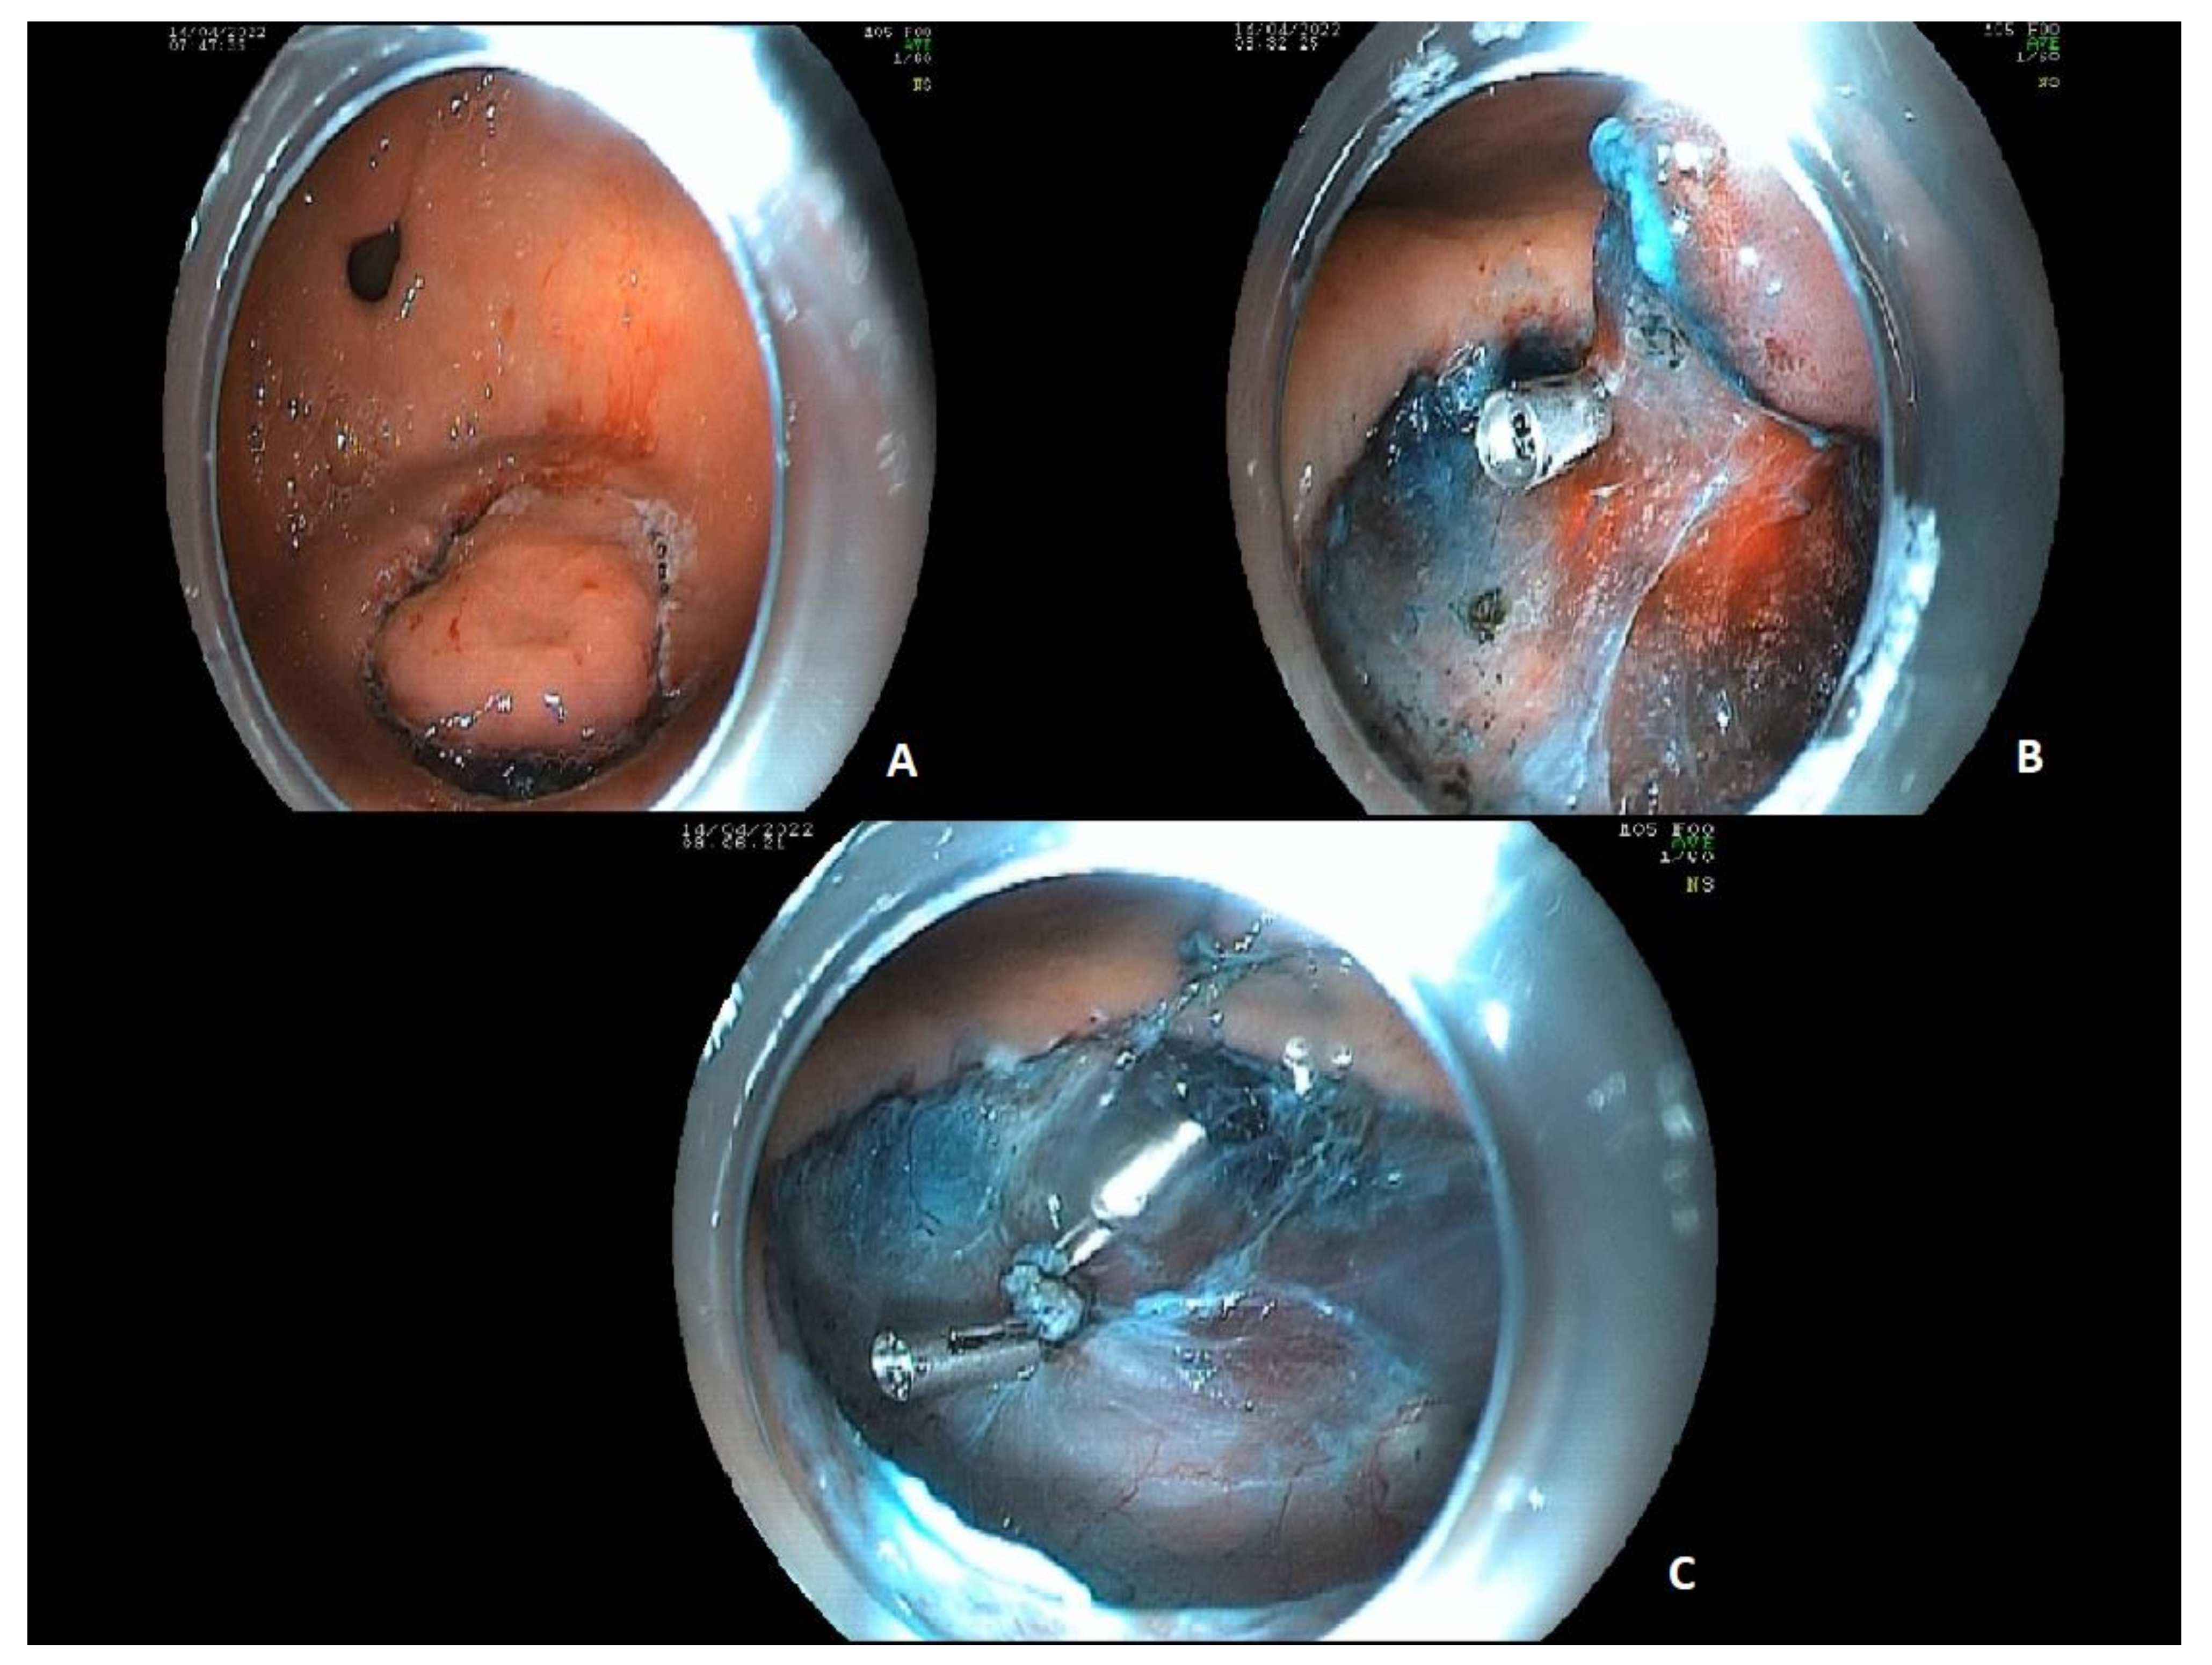

4.1.3. Endoscopic Mucosal Resection and Submucosal Dissection

- Tao, M.; Zhou, X.; Hu, M.; Pan, J. Endoscopic submucosal dissection versus endoscopic mucosal resection for patients with early gastric cancer: A meta-analysis. BMJ Open 2019, 9, e025803. [Google Scholar] [CrossRef]

- Zhao, Y.; Wang, C. Long-Term Clinical Efficacy and Perioperative Safety of Endoscopic Submucosal Dissection versus Endoscopic Mucosal Resection for Early Gastric Cancer: An Updated Meta-Analysis. BioMed Res. Int. 2018, 2018, 3152346. [Google Scholar] [CrossRef]